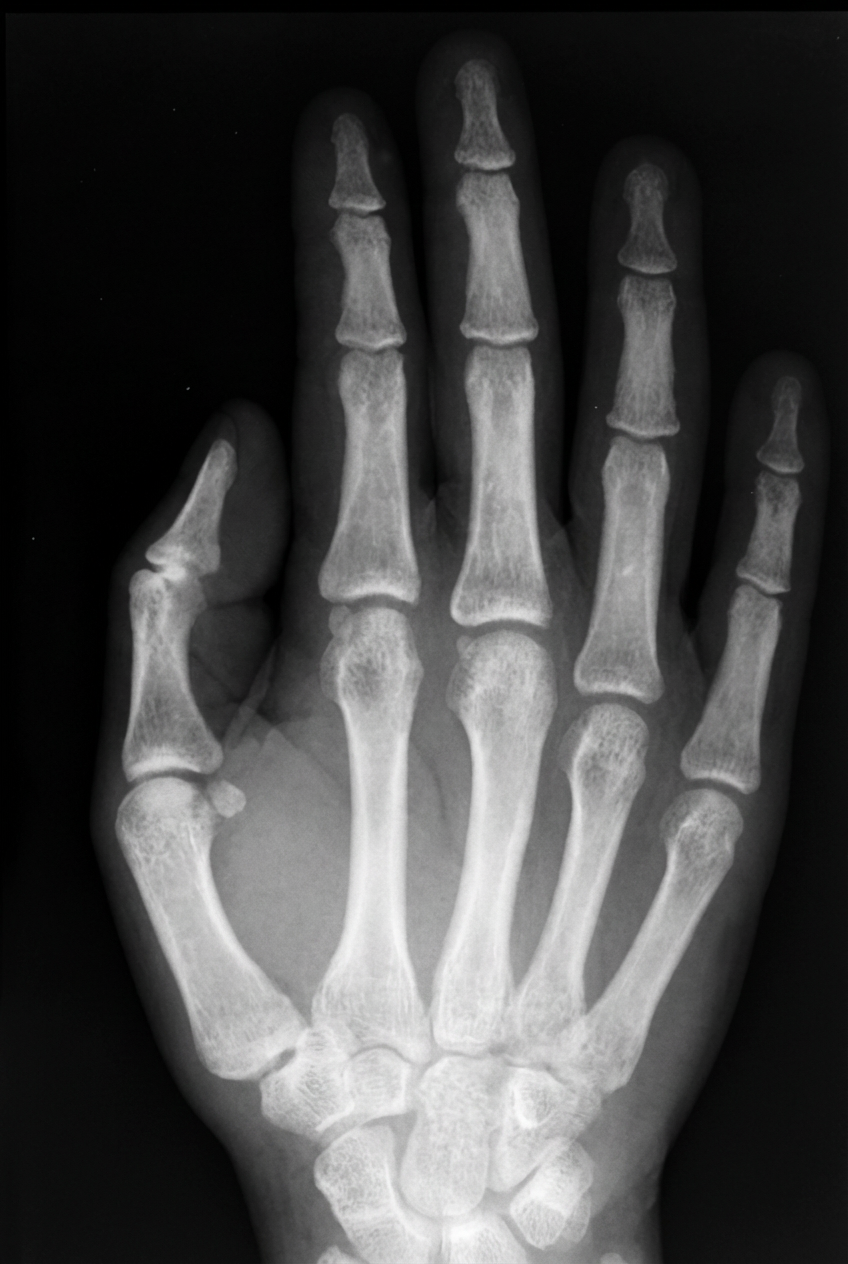

Radiographie des os d’une main humaine. Les os sont lisses et glissants là où ils s’articulent, donnant une excellente dextérité. Image: A. Ciesielski, www.sxc.hu

Lorsqu’on regarde la surface des os, on voit tout de suite que certaines zones sont rugueuses tandis que d’autres sont lisses. Les zones rugueuses sont celles où les muscles sont fixés à l’os, tandis que les zones lisses sont couvertes d’un cartilage glissant où les jointures s’articulent. Imaginez les problèmes que nous aurions si les muscles devaient être fixés aux zones lisses, ou si les zones d’articulation étaient rugueuses. Les muscles s’échapperaient avec une horrible facilité et la douleur de bouger les articulations serait insoutenable. Au lieu de cela, l’os est rugueux exactement là où il doit l’être et lisse exactement là où il doit l’être. C’est bien une caractéristique d’un plan.

Il est remarquable que le squelette humain comporte quatre différentes sortes d’articulations, chacune d’elles étant adaptée à la fonction particulière qu’elle doit remplir. Ces quatre sortes sont: 1) les joints à rotule, qui donnent la liberté de mouvement dans différentes directions (par exemple le fémur et l’os de la hanche); 2) la diarthrose, qui ne permet le mouvement que dans un seul plan (par exemple le genou); 3) la diarthrose rotatoire, qui permet une certaine liberté de mouvement dans plusieurs directions (par exemple le poignet) et 4) les articulations du crâne qui sont inamovibles. Comment un vertébré survivrait-il avec le mauvais type d’articulation au mauvais endroit ?

bougeaient facilement ou si celle du genou était inamovible. Mais non, chacun de ces types d’articulations remplit exactement son rôle. Cela aussi est caractéristique d’un plan.